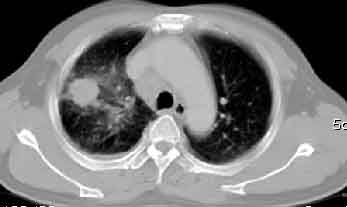

一. 1)症状有无发热及慢性过程.2)化验室检查?3)有无tb接触史?二.右肺上叶见片团状影,边界欠清,外侧方见一结节状软组织影,密度欠均匀,内可见低密度坏死区.周围强化明显,肺内见纤维索条影,局部胸膜增厚,但无明确胸膜凹陷.上叶支气管壁增厚,肺门及纵隔淋巴结增大.右侧胸腔少量积液.诊断意见:1右肺上叶慢性感染性疾病(肺tb?)伴肺门,纵隔淋巴结大.右胸少量积液.右肺上叶结节影多为tb球?2右肺上叶周围型肺ca伴肺门,纵隔淋巴结转移待排.右肺上叶炎变(肺门及纵隔淋巴结压迫).右胸少量积液.等待随返结果.

该病例我的诊断意见:右肺上叶周围型肺癌伴纵隔和右肺门淋巴结增大和右肺上叶阻塞性肺炎{病灶周围致密影以近肺门侧明显!}。右侧少量胸腔积液。

右上肺周围性肺癌,阻塞性肺炎考虑为肿大淋巴结压迫上叶支气管引起。